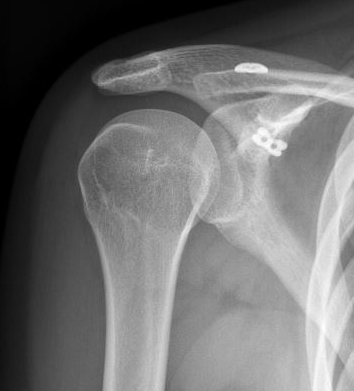

2. Suspensory fixation

Technique

Open or arthroscopic

- drill hole in clavicle

- centred drill hole in coracoid (to avoid fracture)

- reduce AC joint

- tighten suspensory fixation